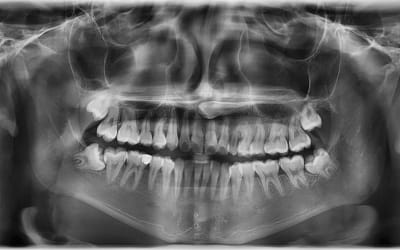

Wisdom Teeth

Are wisdom teeth causing you pain? Here’s what you need to know… Wisdom teeth are the last set of teeth to develop, usually appearing between the ages of 17 and 25. While some people don’t...